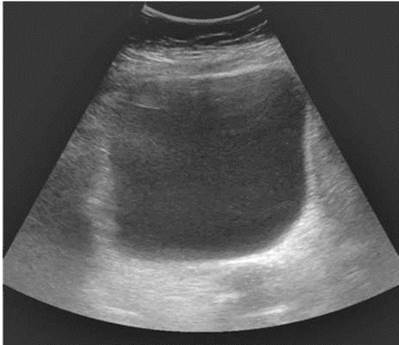

УЗИ почек. Основным доступом при локации почек является кособоковое расположение датчика по средней подмышечной линии. Данная проекция дает изображение почки, сопоставимое с изображением при рентгенологическом исследовании. При сканировании по длинной оси органа почка имеет вид овального образования с четкими, ровными контурами (рис. 4.10).

Полипозиционное сканирование с последовательным перемещением плоскости сканирования позволяет получить информацию обо всех отделах органа, в котором дифференцируются паренхима и центрально расположенный эхокомплекс. Кортикальньгй слой имеет равномерную, несколько повышенную по сравнению с мозговым веществом эхогенность. Мозговое вещество, или пирамиды, на анатомическом препарате почки имеют вид треугольных структур, обращенных основанием к контуру почки и вершиной к полостной системе. В норме видимая при УЗИ часть пирамиды составляет около трети от толщины паренхимы.

Рис. 4.10. Сонограмма. Нормальное строение почки